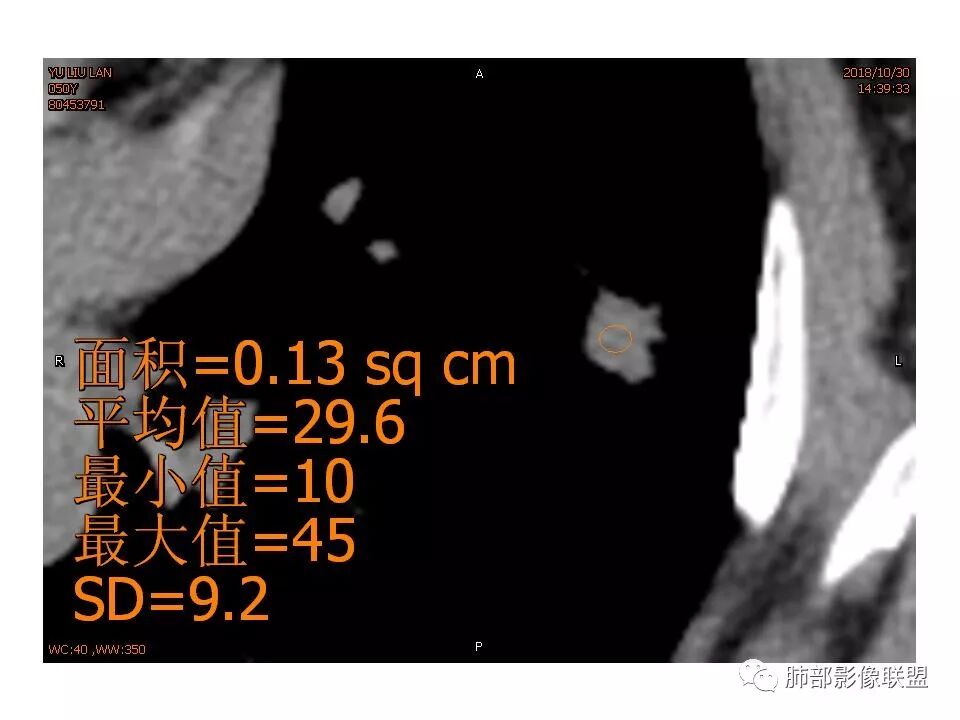

女,50。实性不规则结节,大小12*13mm,分叶、毛刺、胸膜凹陷,牵拉力强,增强渐进性强化,动脉期强化20,静脉期还有进一步强化。边缘强化,点状坏死。

@马宁强杨凌示范区医院放射科 ,不一定准确,看不见血管走行,强化不均匀,有点状第密度。

请问南边老师,这个进入结节的血管算增粗吗?

南边:

稍增粗

恶性征像,胸膜牵拉,浅分叶,毛刺,增强强化明显,净增超25hu。血管边缘模糊串珠样改变。